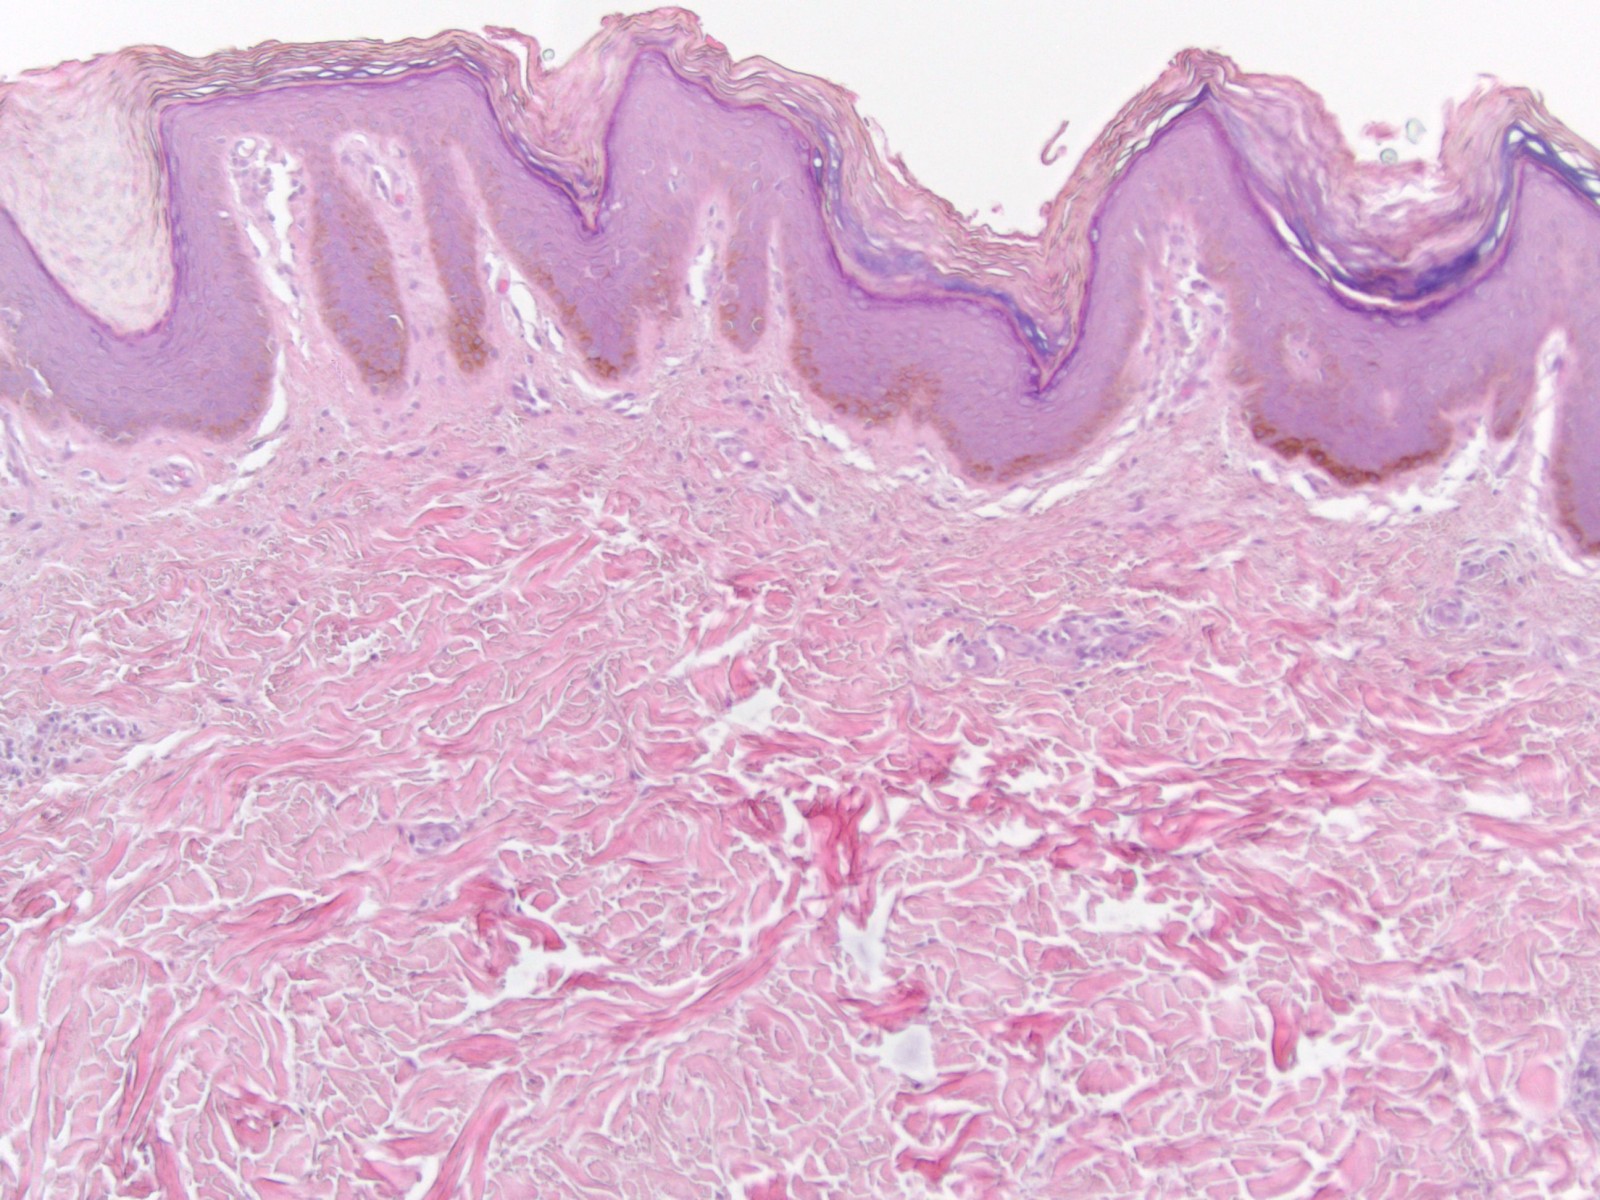

PA: orthokeratose of compacte hyperkeratose, vaak met

gisten (Pityrosporum = Malassezia) in de hoornlaag. Verder kan aanwezig zijn

maar niet altijd een verminderd of afwezig stratum granulosum, papillomatose,

acanthose, en toename van melanine pigment in de basale laag. In de dermis kan

een perivasculair lymfocytair infiltraat aanwezig zijn. Elektronenmicroscopie

toont een verandering in de corneocyten, een verdikte transitional cell layer,

meer lamellar bodies in het stratum granulosum, en meer melanosomen in het stratum

corneum. Immunohistochemicie toont een toename van keratine 16 expressie suprabasaal

en in het stratum granulosum, en toename van Ki-67 in de basale laag.